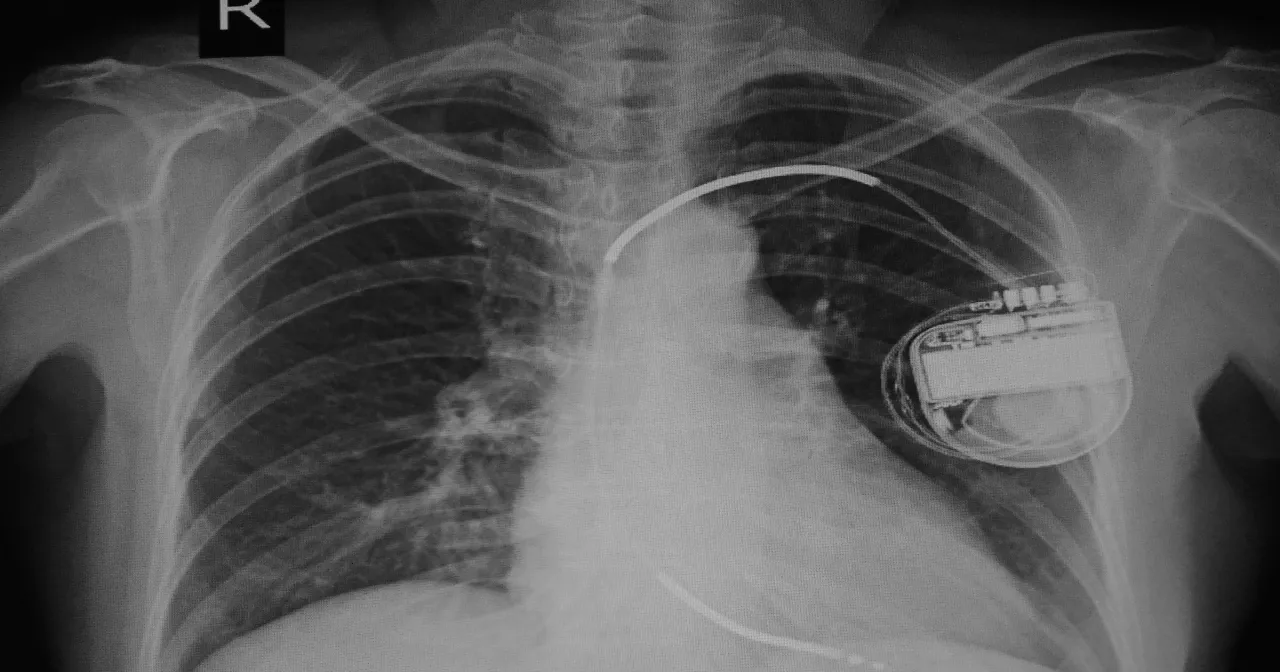

Sam zabieg wszczepienia ICD, choć brzmi poważnie, jest rutynową procedurą dla doświadczonego kardiologa elektrofizjologa. Jest to procedura inwazyjna, ale zazwyczaj wykonywana w znieczuleniu miejscowym, co oznacza, że będziesz świadomy, ale nie będziesz odczuwał bólu. Czasem podaje się również leki uspokajające, aby zwiększyć Twój komfort. Lekarz wykonuje niewielkie nacięcie, najczęściej w okolicy obojczyka. Następnie, pod kontrolą promieni rentgenowskich (RTG), elektrody są wprowadzane przez żyłę podobojczykową bezpośrednio do serca. Kiedy elektrody znajdą się w odpowiednim miejscu i zostaną przetestowane, generator (czyli "puszka") jest umieszczany pod skórą, najczęściej w okolicy obojczyka. Cały zabieg trwa zazwyczaj od 40 minut do kilku godzin, w zależności od złożoności przypadku.